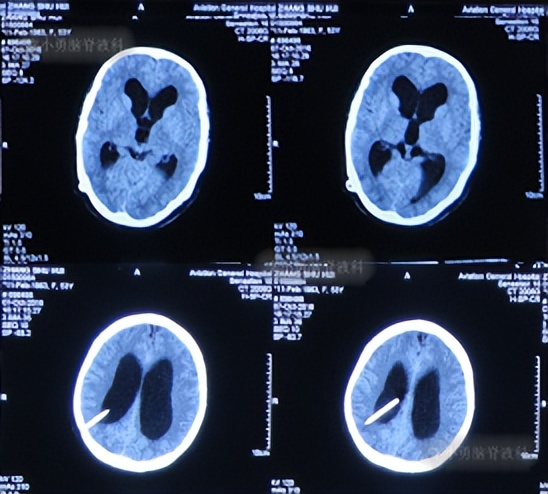

第2次术后40天即2016年12月3日,头颅CT:脑室较入院时明显缩小( 图-18 )。

图-18: 头部CT 对比图